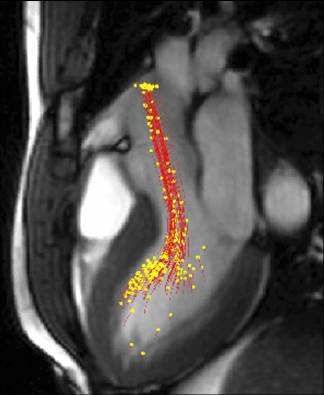

| We can study mechanical function: | Regions of motion abnormalities are readily visualized: Myocardial Infarction vs Healthy |

|

(click on the image to view animation) |